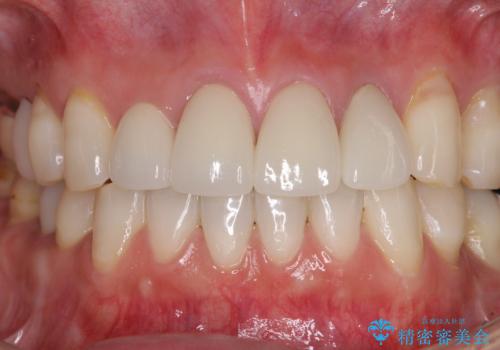

目立つ範囲である前歯4歯をオールセラミッククラウンにて補綴することとしました。

口元の印象が明るくなり、人前で気にせずに笑えるようになりました。